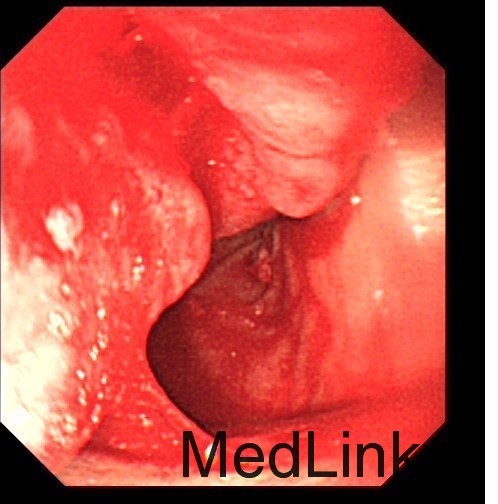

查体: 面色稍苍白,皮肤黏膜及巩膜无黄染,浅表淋巴结未及肿大,无肝掌及蜘蛛痣,无浅表静脉曲张,右上腹肋缘下处可触及一约5cm*5cm包块,界清,质软。 辅查: 电子胃镜:十二指肠降段溃疡未排恶变,病理诊断(十二指肠降段)粘膜组织呈慢炎性 腹部CT平扫+增强:胰头部肿块,考虑囊腺瘤可能性大。

患者慢性贫血与消化道长期失血有关,当地仅凭一次胃镜活检未提示恶性病变,便只以良性病变诊治,应该说不全面。对于向腹腔外生性生长的肿瘤,内镜很多时候取不到合适的标本,此时需借助增强CT等影像学评估肿瘤生长情况。